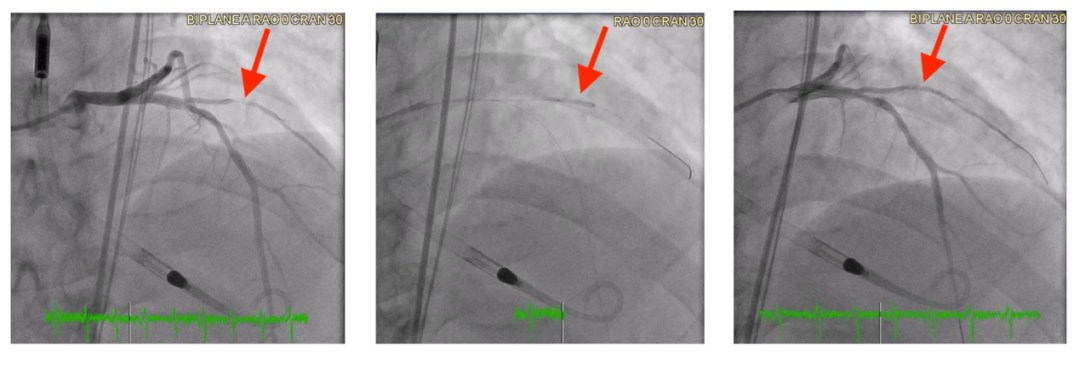

图7冠状动脉造影图像显示了使用DCB治疗涉及开口第一斜支90%狭窄的原发性小血管冠状动脉疾病。

注:(A)治疗前图像显示第一斜支开口处90%狭窄。(B)置入一个2.5×12mm的DCB,在4个大气压下持续60s。(C)治疗后图像显示,DCB干预后狭窄程度降至30%,血管通畅性得到改善。